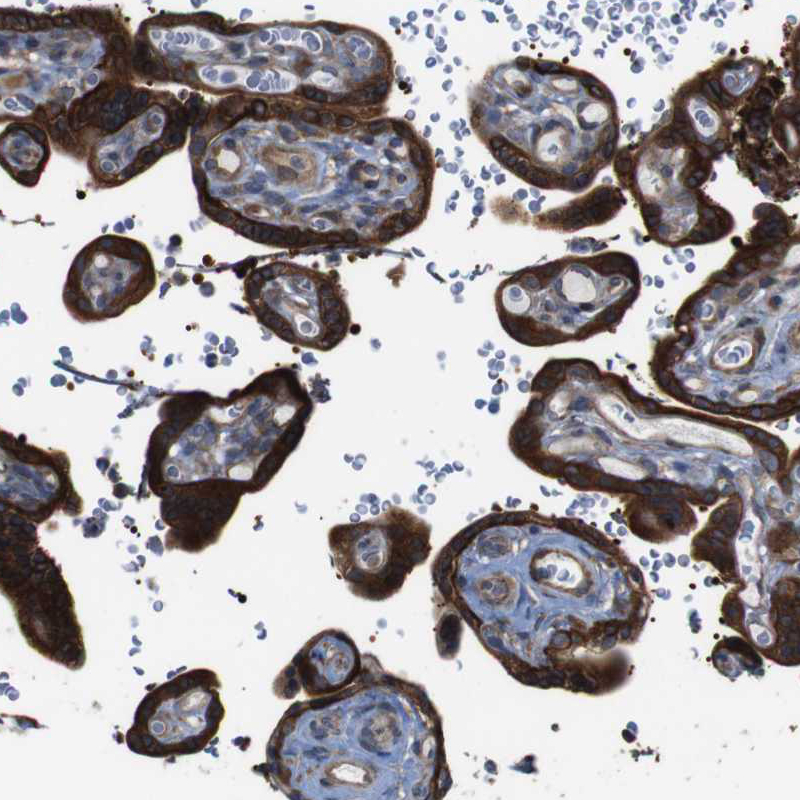

Immunohistochemical staining of human placenta shows strong cytoplasmic/membranous positivity in trophoblastic cells.